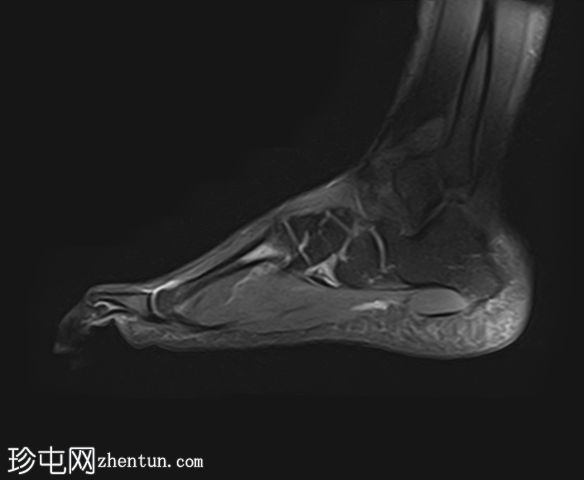

PD脂肪抑制

矢状位

STIR序列

质子密度(PD)脂肪抑制像显示第二跖骨干骨髓水肿,伴骨膜及周围软组织水肿。未见明确的皮质骨折线。

第二跖骨应力性骨折,根据Fredericson分级,MRI分级为3级,伴骨膜及周围软组织水肿。